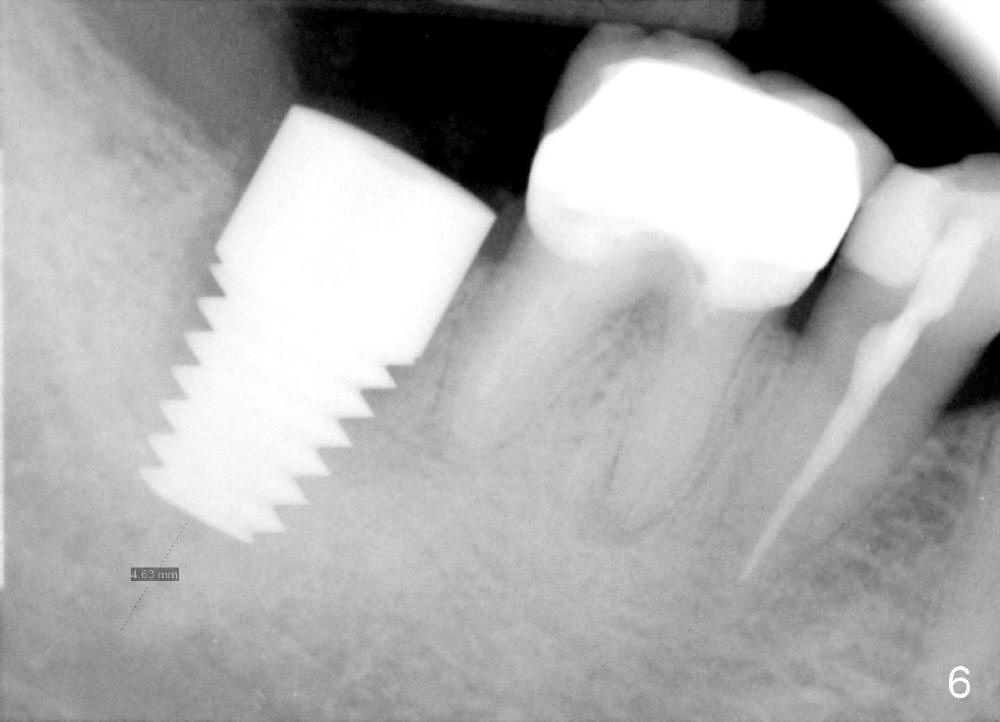

A 51-year-old man has experienced pain and swelling in the lower right 2nd molar for 7 months (Fig.1, P: post in the mesial root; <: gutta percha inserted into a buccal fistula). Fig.2 is taken immediately before extraction (<: purulent discharge from the mesiobuccal fistula) and immediate implant (Fig.3 implant design: 7x14 mm). A vertical root fracture is noted in the mesial root (Fig.4: lingual view). The septum is in fact absent, as compared to Fig.1. The mesiobuccal plate is low; the osteotomy starts lingual to the center of the socket. Fig.5 shows a 4.5x17 mm tap in place: approximately 3.5 mm in the new bone (~2.5 mm from the inferior alveolar canal). When a 7x17 mm tap (14 mm from the gingival margin) is placed in the socket, it looks relatively small. Fig.6 shows a 8x14 mm implant in place with a small gap distally. Mineralized cancellous allograft and Osteogen mixture is placed mainly buccally, followed by a thin strip of collagen dressing and sutures (Fig.7); an abutment (A) is placed to keep perio dressing in place. The perio dressing does not stay long. The buccal portion dislodges by itself 5 days postop. The lingual portion is removed in clinic. New dressing is going to be re-applied, because the buccal wound has not completely healed (Fig.8 <, albeit asymptomatic) with partial exposure of the bone graft (*). Why is the dressing lost so early? The abutment is not long enough; there is plenty of occlusal clearance (Fig.9 arrows). A longer abutment is used to increase mechanical retention for perio dressing (Fig.10). By the time the second perio dressing dislodges, the wound has healed (Fig.11, 13 days postop).

The patient returns for final restoration 5.5 months postop; it appears that the distal gap has disappeared (Fig.13 *). There is no bone loss 26 months post cementation (Fig.14). The lamina dura-like dense bone forms coronally 3 years 4 months post cementation (Fig.15 *). The 8 mm implant remains buried in the bone 5 years 4 months post cementation (Fig.16).